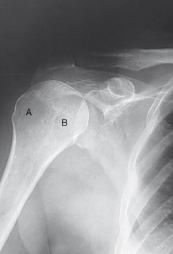

label the anatomy accordingly A-E, the projection/part, and rotation if applicable

acromion, coracoid process, inferior angle, spine of scapula, body of scapula

PA oblique